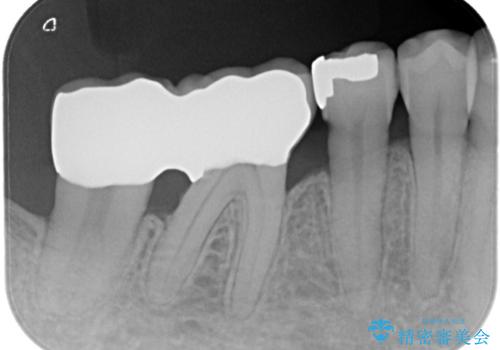

【PGAインレー】深い位置の二次カリエス

- 定期検診にて虫歯を発見したため、PGAインレーにて治療を行いました。

PGAインレーは金と白金を多く含み、精度高い修復が可能です。